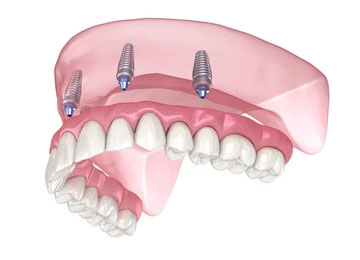

骨の弱い方や、骨が柔らかい方には、インプラント6本で歯を支えるオールオン6がお勧めです。

オールオン6とは、6本のインプラントで12本の歯を支える治療方法です。

この方法は、日本人のように顎の骨が比較的やわらかいケースで採用されることが多く、オールオン4との主な違いは、使用するインプラントの本数が4本か6本かという点にあります。

そのため、オールオン4を希望される患者さんでも、骨の状態によっては6本のインプラントで治療を行う方が、より安定して長く使用できる場合があります。